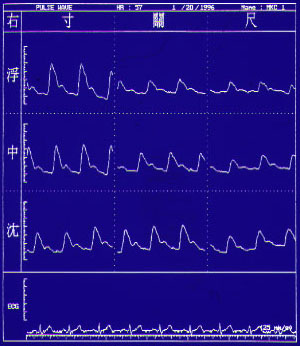

右脈寸關尺,浮中沉

右關脈及尺脈皆沉脈,但右寸脈為浮脈且滑脈。